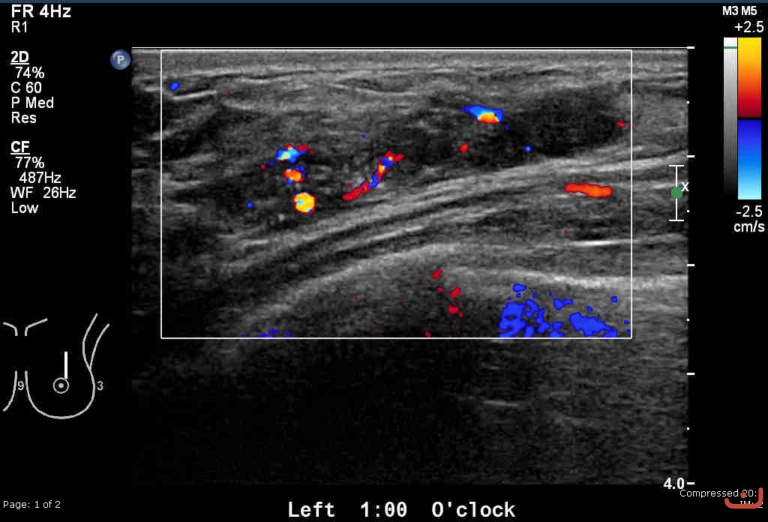

Malignant solid mass

Friday, 22 May 2015

214.97 KB (768 x 522 px)